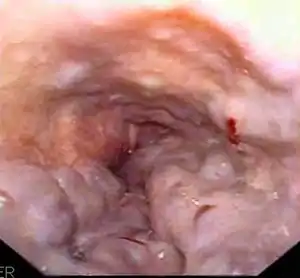

![]() | |

| Gastroscopy image of esophageal varices with prominent cherry-red spots and wale signs | |

Esophageal varices are extremely dilated sub-mucosal veins in the lower third of the esophagus.[1] They are most often a consequence of portal hypertension,[2] commonly due to cirrhosis.[3] People with esophageal varices have a strong tendency to develop severe bleeding which left untreated can be fatal. Esophageal varices are typically diagnosed through an esophagogastroduodenoscopy.[4]

Dilated submucosal veins are the most prominent histologic feature of esophageal varices. The expansion of the submucosa leads to elevation of the mucosa above the surrounding tissue, which is apparent during endoscopy and is a key diagnostic feature. Evidence of recent variceal hemorrhage includes necrosis and ulceration of the mucosa. Evidence of past variceal hemorrhage includes inflammation and venous thrombosis.